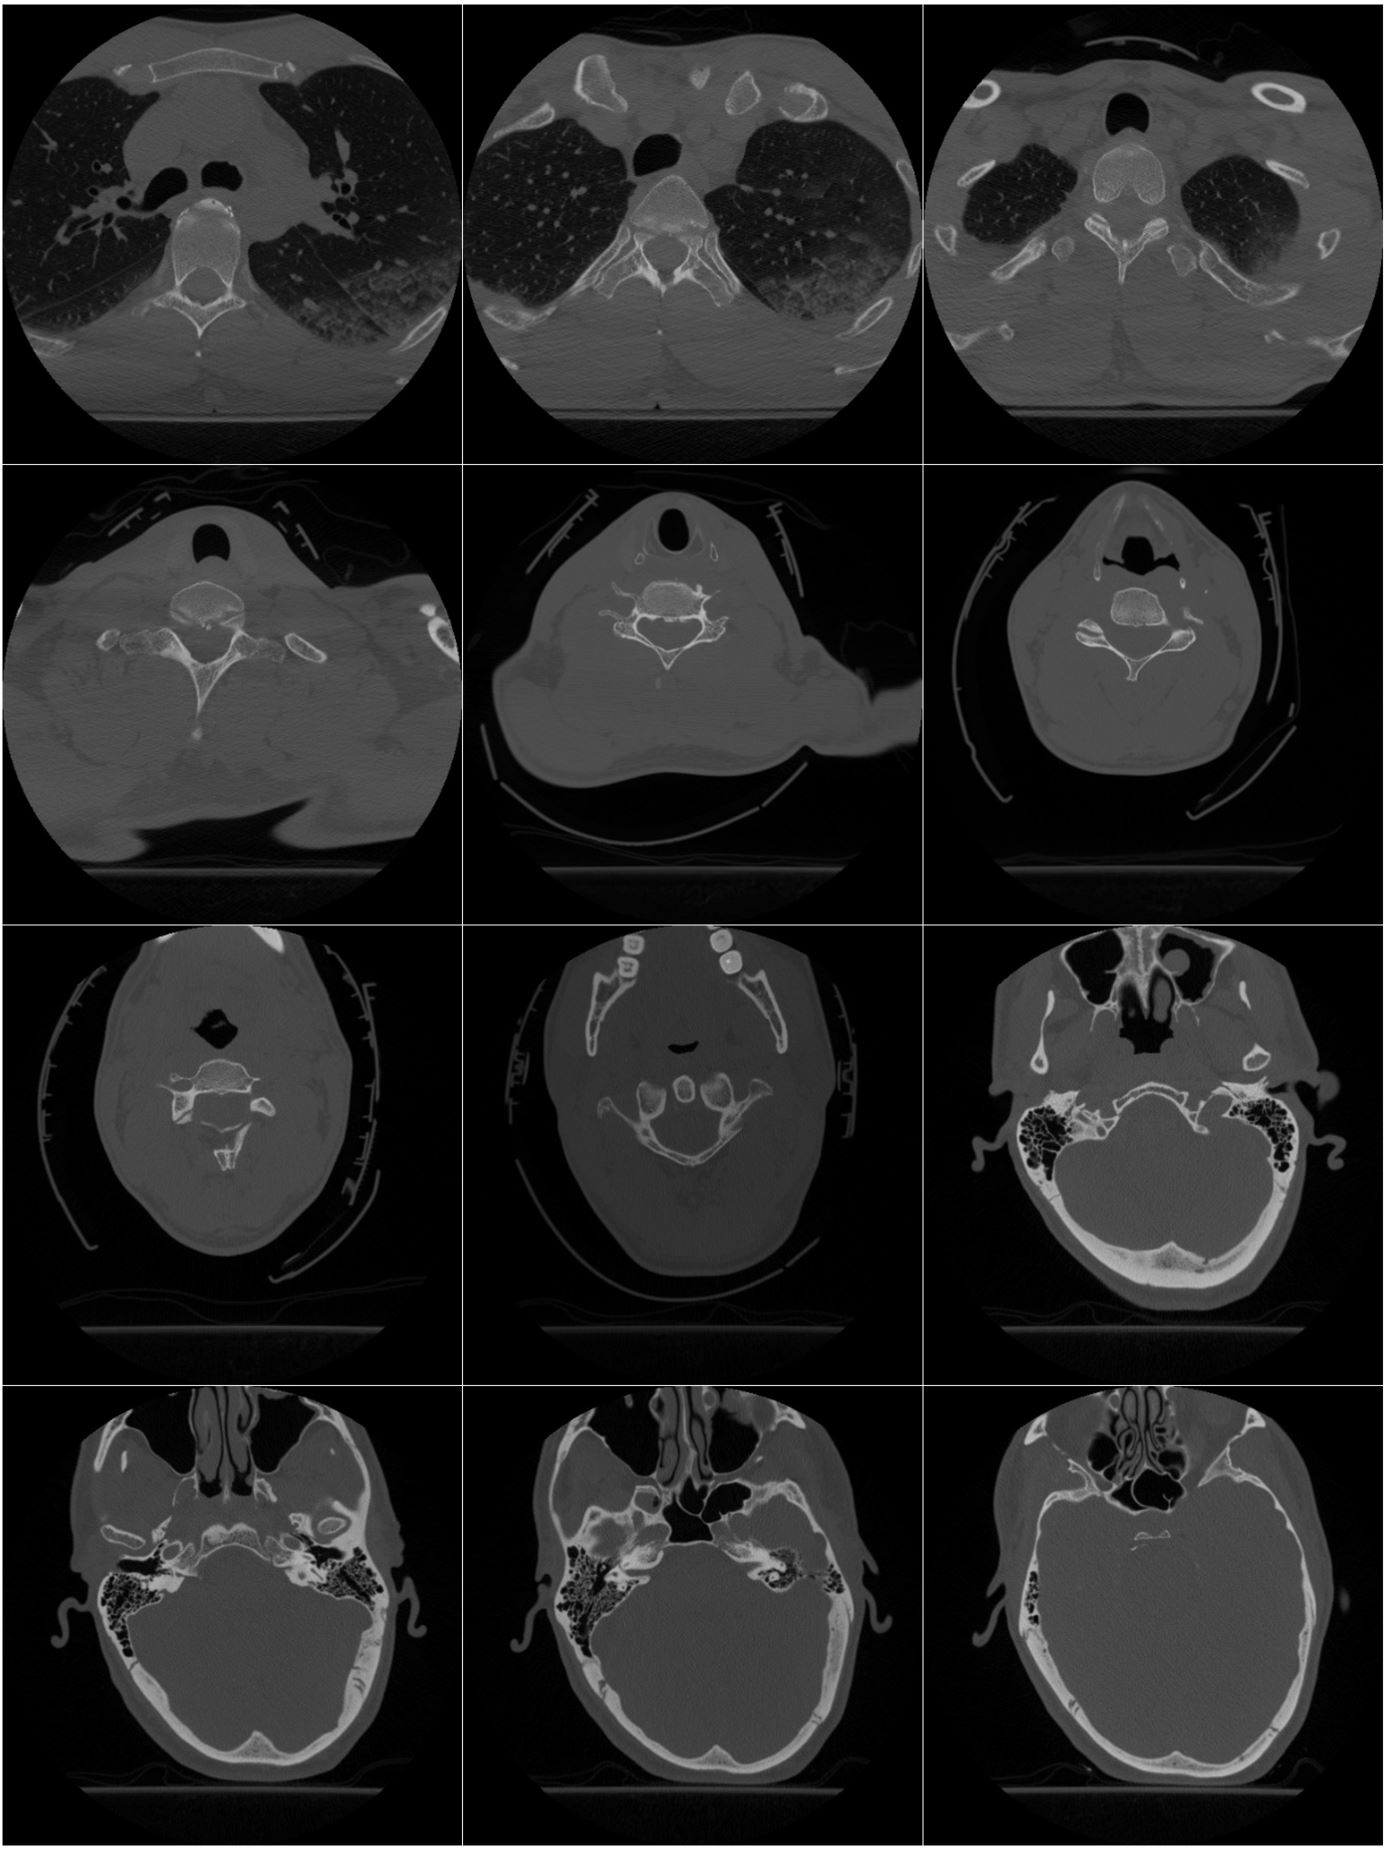

Figure 3 shows some MRI images of this model.